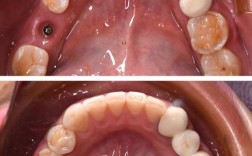

(图片来源网络,侵删) - 医生的经验和资质: